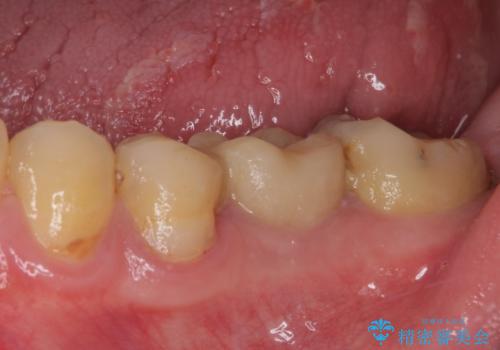

セラミッククラウンによる奥歯のむし歯治療

- 奥歯がしみて痛いとのことで来院された患者様です。

既に複数箇所の修復が行われていたため、オールセラミッククラウンにて補綴をすることとしました。

以前装着した修復物が不適であり、歯肉が腫れていましたが、仮歯を装着したことで腫れは解消されました。

歯の痛みだけでなく、歯肉の腫れも改善され、患者様には大変満足していただきました。